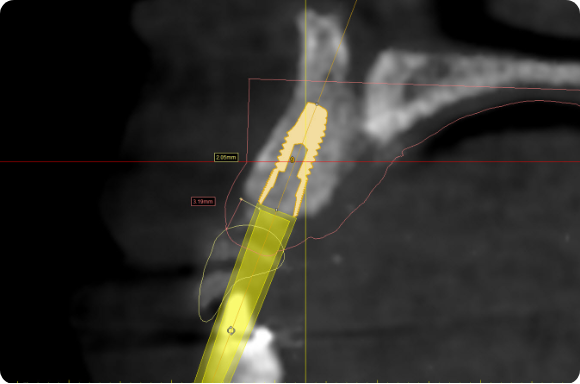

Utilizing procedure-based education1, this level will help the clinician grow into more advanced surgical and prosthetic concepts with the treatment of single tooth anterior implant cases

Throughout this level, the cases will cover topics including: Evaluating buccal and apical bone for immediate placement, Grafting around immediate implants (Dual Zone Technique), Defining implant orientation – The Rules of Six, Assessing primary stability for immediate provisionalization, CAD/CAM abutment options and designs. At the completion of this level, participants will understand how to place and restore a single-tooth implant in the anterior zone. Participants are encouraged to continue their education in Level 4, which will focus on multi-unit cases.